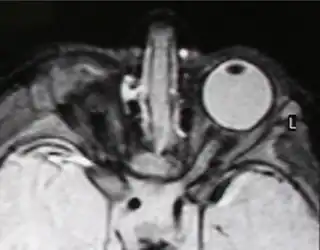

IRM de anoftalmía unilateral

La anoftalmía es la ausencia completa de uno o ambos ojos. [1]

Cuando el ojo existe en el momento del nacimiento, pero está muy poco desarrollado, el término que se utiliza para referirse a esa situación es microftalmía. La microftalmía congénita es más frecuente que la anoftalmía.

Un estudio realizado en Inglaterra entre los años 1988 y 1994 mostró que la incidencia conjunta de ambos trastornos era de un caso por cada 10 000 nacimientos. Tanto la anoftalmía como la microftalmía congénita pueden ser unilaterales o bilaterales y suelen asociarse a una órbita poco desarrollada, ausencia de párpados y de la glándula lagrimal en la hemicara afectada.[2]